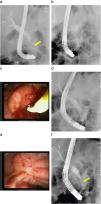

Figura 1. a) Estenosis filiforme de colédoco distal de 20mm de longitud (flecha). b) Prótesis metálica recubierta de 10×40mm recién colocada con vaciamiento completo del contraste de la vía biliar. c) Papila mayor con reacción inflamatoria, y sin visualizar la prótesis metálica. d) Prótesis metálica expandida completamente en el borde de la papila y migrada hacia el interior del colédoco. e) Escara de resección de papila mayor 10 días después. f) Estenosis de colédoco distal dilatada tras retirada de la prótesis (flecha), con un calibre de 4mm.

Se revisó al paciente a los 2 meses y refería dolor abdominal difuso. En la analítica realizada se observó elevación de amilasa con perfil hepático normal. En la duodenoscopia se veía la papila mayor con reacción inflamatoria sin que se consiguieran ver los filamentos de la prótesis (figura 1c), aunque se podía visualizar la prótesis metálica expandida en el borde de la papila mediante la radiología (figura 1d). Se intentó extraer con balón de Fogarty y pinza de cuerpos extraños sin éxito. Ante esta situación, se despegó parcialmente la prótesis mediante needle knife para dejarla visible. El paso siguiente fue la resección parcial con asa de la circunferencia papilar y el intento de movilización de la prótesis mediante pinza de cuerpos extraños. Se continuó con la resección piecemeal peripapilar y se dio argón en el tejido intraprotésico; finalmente, se consiguió sacar la prótesis mediante un asa de polipectomía.

A las 48h apareció hemorragia del borde de la papila mayor, que se controló mediante la inyección de adrenalina 1:10.000 inicialmente y con suero fisiológico; tras el cese de la hemorragia se colocó una prótesis plástica biliar con el fin de evitar complicaciones por el coágulo y la inyección papilar. A la semana se revisó y se pudo apreciar la escara de papilectomía con fibrina (figura 1e) y la expulsión espontánea de la prótesis biliar, junto con la presencia de un buen calibre de la estenosis (figura 1f). Durante su seguimiento en 9 meses, presentó una bioquímica hepática normal sin dilatación de la vía biliar por ecografía y se obtuvo un calibre final de la estenosis superior al conseguido con prótesis plásticas.